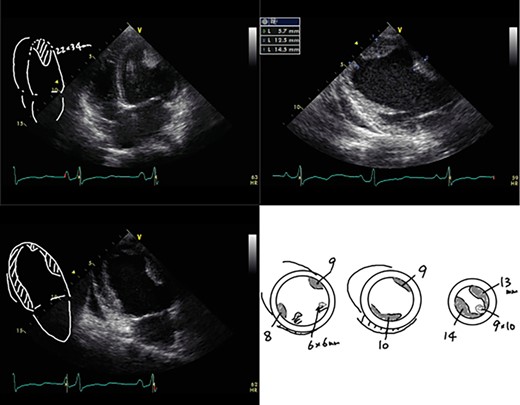

A 23-year-old woman presented with dyspnea after giving birth to her second child at a local hospital. Edema of both lower limbs gradually appeared, her labored breathing worsened, and the left ventricular ejection fraction (LVEF) was <30% by echocardiography. She was diagnosed with PPCM 5 months after childbirth. The LVEF had decreased to 10% and a left ventricular apical thrombus was also observed by echocardiogram (Fig. 1). She was transported to our institution due to progressive severe heart failure, and treated with intravenous inotropes, extracorporeal membrane oxygenation (ECMO) and intra-aortic balloon pumping (IABP). The LVEF subsequently decreased to 7% and left ventricular enlargement with multiple mural thrombi was observed. The condition was INTERMACS profile 1, and a LVAD was indicated. In Japan, an implantable LVAD can be applied only in patients in whom registration for heart transplantation has been already approved and the patient had no chance for an implantable LVAD. Thus, we implanted an external LVAD (AB 5000, ABIOMED, Danvers, MA, USA).

After the surgery, she received medical therapy consisting of carvedilol, 25 mg daily; enalapril, 5 mg daily; and bromocriptine, 5 mg daily for 2 weeks and 2.5 mg daily for 6 weeks, and her heart failure was controlled using furosemide, spironolactone and tolvaptan in combination. Aspirin (100 mg/day) and Warfarin (PT-INR 2.5-3.0) was also administered. Although her PT-INR had been strictly controlled within the therapeutic range, she had suffered from minor strokes several times. The N-terminal pro-brain natriuretic peptide level (NT-proBNP) improved from >5000 to <200 pg/ml in 2 months, and LVEF accordingly improved to 30%. She was smoothly recovering from wheel chair sitting position to walking through daily rehabilitation trainings. Based on her cardiac and general improvement and refractory minor strokes, the heart team decided to explant the LVAD. A LVAD withdrawal test was performed 2 months after the surgery, indicating that turning off the LVAD did not significantly affect cardiac function as well as water loading. NT-proBNP level temporarily increased but then gradually improved, and cardiac function also recovered to LVEF 42% after the LVAD removal (Fig. 2). One month later, she was transferred to a local hospital to continue her rehabilitation and finally discharged home. At 1 year after the symptom onset, she is suffering from NYHA II heart failure, but she was able to do normal daily activities, including raising her children. She gave informed consent for the publication of this report.

Serum NT-proBNP levels and the left ventricular ejection fraction (LVEF).